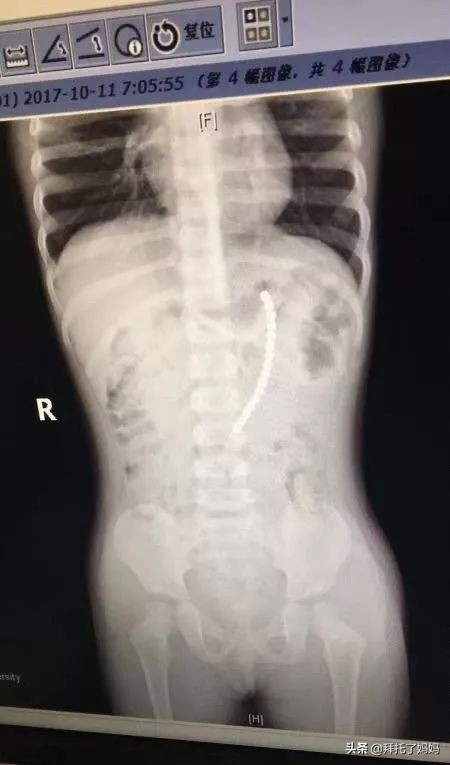

复旦大学附属儿科医院医生给这个小女娃拍了片子,结果,人们惊呆了!

一共有19颗珠子在体内!!

复旦大学附属儿科医院副院长、儿外科专家郑珊团队,给孩子做了胃镜,取出了胃里的六颗巴克球,但发现有一排珠子已经穿出胃壁,到外面去了。

在腹腔镜下发现

剩余的珠子一颗连一颗构成一串

一端在胃里,另一端在小肠里

也就是说

孩子肠子和胃里面

都被巴克球穿孔了!

医生取出珠子后

再把小女娃的胃和小肠补上